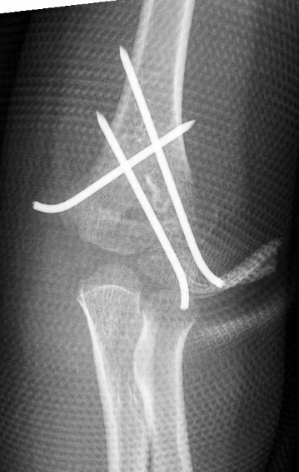

1、小红(化名):女、6岁、吊单杠时不慎摔伤致左肘部肿痛、畸形、活动受限2小时就诊我院。(下图为患儿术前X线片及CT检查)

此种类型的骨折称为肱骨髁上骨折,在完善相关辅助检查后予行麻醉下平乐郭氏手法正骨经皮钢针内固定治疗,术后患儿恢复良好,手术部位只有几个小针眼。(下图为患儿术后X线片)